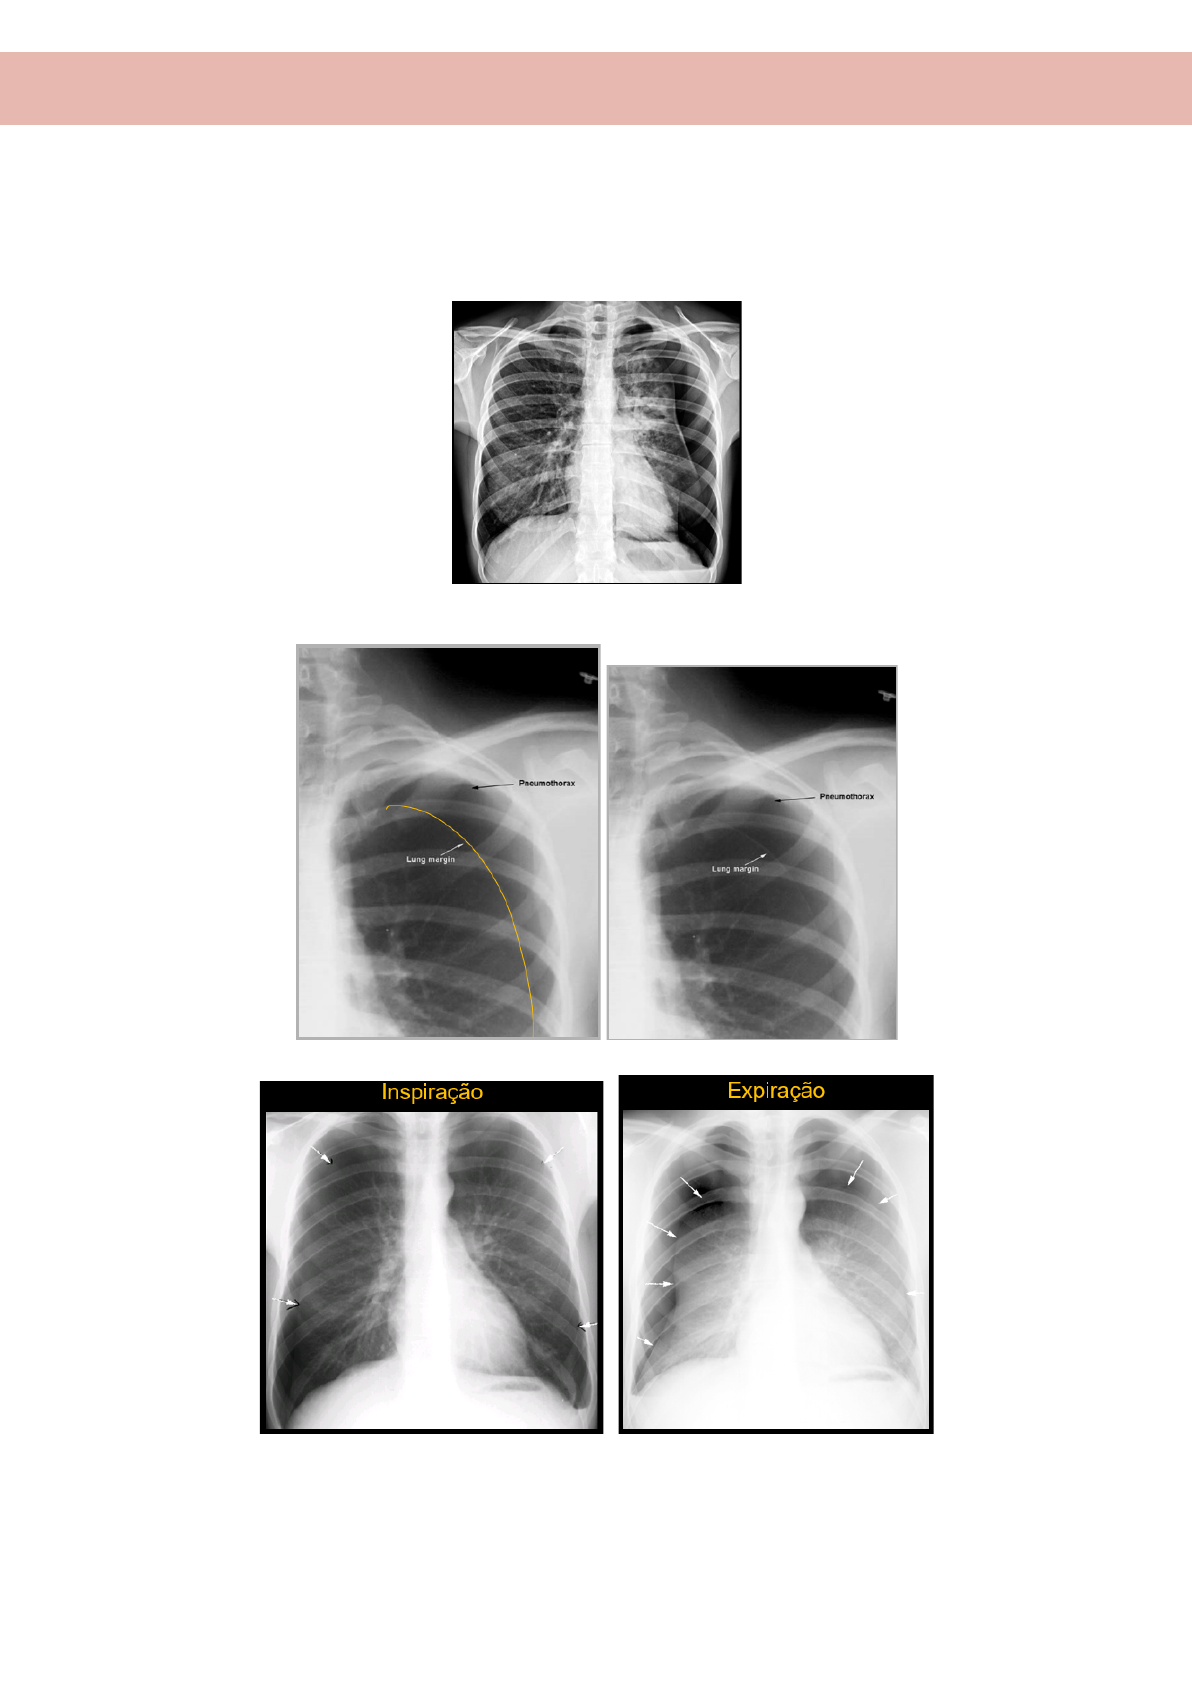

● PNEUMOTÓRAX

Problema no hemitórax esquerdo

É importante pedir em inspiração e expiração para conseguir distinguir as margens

Posso aumentar a área de exposição ao raio da máquina, para conseguir ver os limites melhores do pneumotórax

Pneumotórax

RX AP no leito

- sinal do sulco profundo

● CORPO ESTRANHO

- Hiperinsuflação unilateral

Paciente chega com desconforto respiratório;

no RX aparece uma hiperinsuflação unilateral

pede RX em ins e exp;